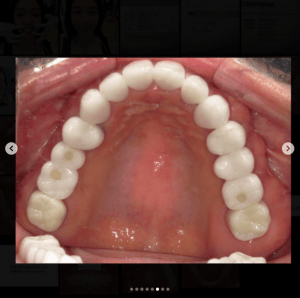

審美歯科症例集(ビフォーアフター)

より多くの症例をこちらのページでご紹介しておりますので、合わせてご覧ください

Case032

広島からの患者様です。

前歯を綺麗にしたい。インプラントをしたい。

という主訴で東京の歯医者をいろいろ調べて当院を選んでくださいました。

毎回、遠い中しっかり通ってくださり、選んで頂けた嬉しさと、その気持ちに応えたいという想いで診療させて頂きました。

前歯はご希望のお色でラミネートベニアでは出せない透明感のあるセラミックに上下左側7はインプラントをさせて頂きました。

左上は破折で温存不可。

骨も少なかったので、サイナスリフトも行い計五回の来院で被せ物を入れさせて頂きました。

左下は前回のクリニックでの埋入位置が深すぎて食べカスも毎回詰まる、セルフメンテナンスではら汚れも取れない。インプラント周囲炎にもなっていたので、一度前のインプラントを除去し、そこから新しくインプラントを埋入し、診療させて頂きました。

インプラント、歯並び、審美歯科にご興味のある方はいつでも相談にお越しください。

担当 理事長 佐藤 悠野